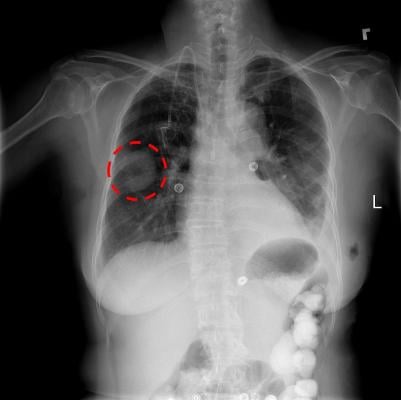

Researchers at the Icahn School of Medicine at Mount Sinai assessed how AI models identified pneumonia in 158,000 chest X-rays across three medical institutions: the National Institutes of Health; The Mount Sinai Hospital; and Indiana University Hospital. Researchers chose to study the diagnosis of pneumonia on chest X-rays for its common occurrence, clinical significance and prevalence in the research community.

In three out of five comparisons, CNNs’ performance in diagnosing diseases on X-rays from hospitals outside of its own network was significantly lower than on X-rays from the original health system. However, CNNs were able to detect the hospital system where an X-ray was acquired with a high-degree of accuracy, and cheated at their predictive task based on the prevalence of pneumonia at the training institution. Researchers found that the difficulty of using deep learning models in medicine is that they use a massive number of parameters, making it challenging to identify specific variables driving predictions, such as the types of computed tomography (CT) scanners used at a hospital and the resolution quality of imaging.